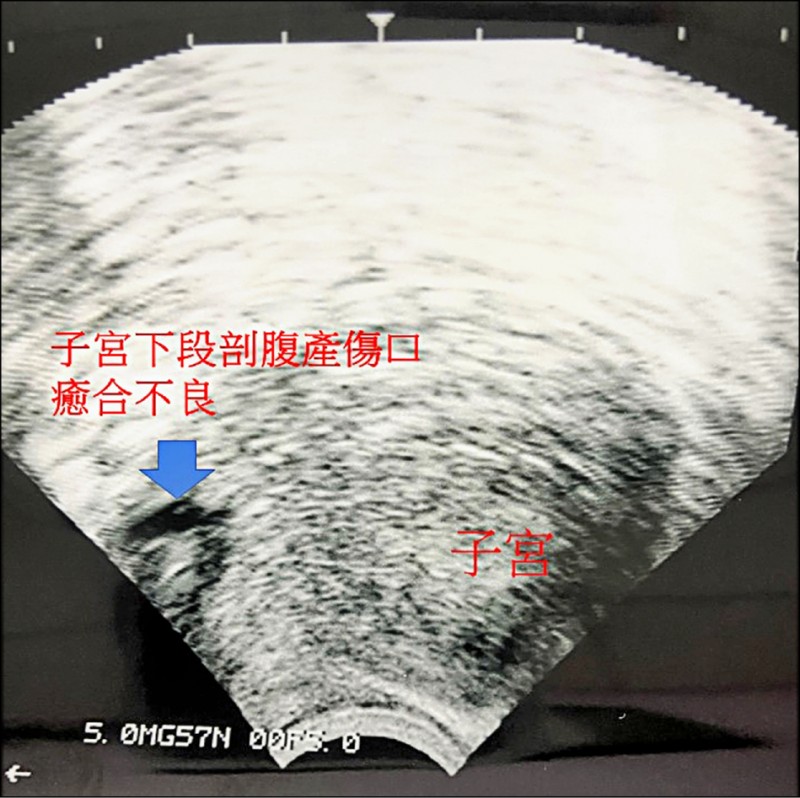

剖腹傷口癒合不良 產後月經滴滴答答...